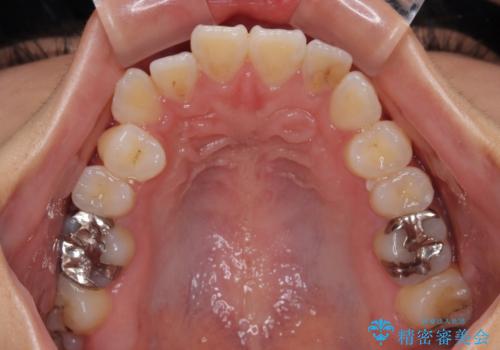

舌の突出癖が原因 インビザライン矯正による開咬改善

- 矯正装置

- インビザライン

- 前歯の開咬を気にして来院された患者様です。

開咬の治療は、前歯を閉じるように動かすとともに、上下臼歯を圧下(骨内にめり込ませる)させることで進めて行きます。

インビザラインは臼歯の圧下を効果的に行えるため、インビザラインを用いて矯正治療を行うこととしました。